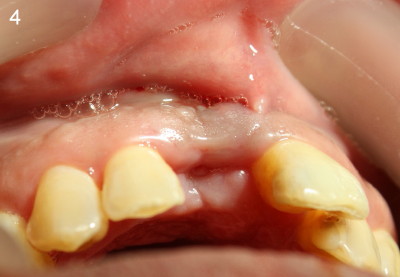

The patient is scheduled to return 1 week later for #8 socket debridement and irrigation.  The labial aspect has undergone atrophic changes (Fig.3,4).  More surprisingly is that the labial plate is found to be lost during socket debridement.  The labial plate seems to be intact at extraction.  Otherwise socket preservation must have been done.

Does this post-extraction infection happens often, but without being noticed?  Four quadrant scaling and root planing should have been conducted prior to extraction to reduce infection in this case. Note calculus in the lower anteriors (Fig.1).   Does immediate implant with bone graft prevent loss of the labial plate?   What should we do for this case now?  Wait for 2-3 months before implant placement?  Or bone graft after the infection is under control?